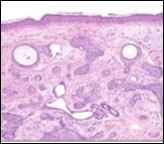

Figure 1.Desmoplastic trichoepithelioma demonstrating aggregates of basaloid cells with numerous keratinous horn cysts interspersed in an intensely fibrotic stroma 9.

Figure 2.Desmoplastic trichoepithelioma delineating cords and nests of basaloid cells, few horn cysts and a circumscribing fibrotic stroma 9.

Desmoplastic trichoepithelioma is challenging to discern on clinical and histological grounds, especially when evaluated with miniature, superficial, shave tissue samples. Thus, deep-seated tissue sampling is required. Brownstein and Shapiro in 1977 delineated the morphological features of desmoplastic trichoepithelioma as configuring narrow strands of basaloid tumour cells, keratinous cysts and an encompassing desmoplastic stroma. Aforesaid features exemplify a unique histological triad categorizing desmoplastic trichoepithelioma. Enunciation of a thin walled, attenuated epidermis and an absence of superficial telangiectasia assists the discernment of desmoplastic trichoepithelioma 3, 4.

On gross examination, frequently the tumours are gradually progressive, grey/white or flesh coloured, indurated, non ulcerated with a central depression and a magnitude varying within a few millimetres. The well circumscribed lesion is symmetrical, confined to papillary dermis and upper two thirds of reticular dermis. Emergence of narrow strands of basaloid epithelial cells, numerous horn cysts, a dense, encompassing fibrous tissue stroma, foreign body granulomatous reaction, several foci of calcification and articulation of osteoma within the lesion provide diagnostic characteristics 3, 4.

Nests, strands and miniature cords of basaloid epithelial cells of variable dimension, encompassed within a dense fibrotic tissue stroma are observed within the upper and mid-dermis. Cellular aggregates are rimmed with collagen bundles, multiple horn cysts appear within the stroma and a layering of stratified squamous epithelium is enunciated. Foci of calcification are apparent. Mitotic figures, peripheral palisading, apoptotic bodies aggregated within the epithelium or cellular and nuclear pleomorphism are absent 3, 4

Commonly, miniature strands of basaloid cells are encompassed within a desmoplastic stroma in association with keratinous cysts, usually abutting or attached to basaloid cell aggregates. Superimposed epidermis demonstrates a mild atrophy in accompaniment with enlarged cords of tumour cells aggregated within the mid - dermis. Connective tissue hyperplasia is observed within the horn cysts 4, 5.

Lesions are generally superficial and infrequently invade lower dermis. Tendency for peri-neural or intra-neural infiltration, cogitated in adjunctive cutaneous carcinomas, is exceptional in desmoplastic trichoepithelioma. Nevertheless, desmoplastic trichoepithelioma can be exemplified as a component of particularly desmoplastic, cutaneous carcinomas demonstrating foci of peri-neural involvement 4, 5. Figure 1, Figure 2, Figure 3, Figure 4, Figure 5, Figure 6, Figure 7, Figure 8.